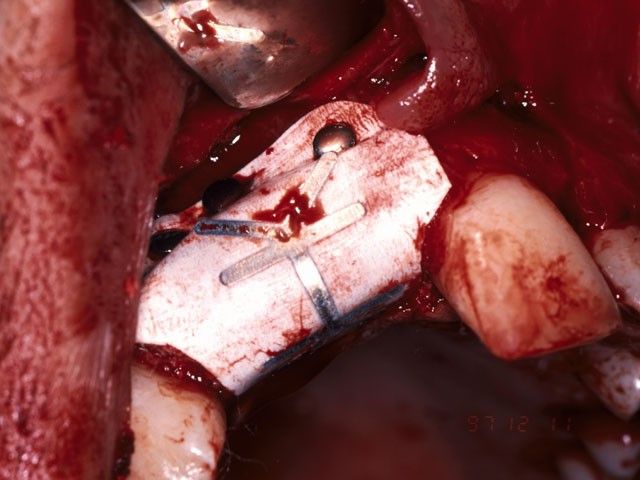

Από το 1992, ο χειρουργός οδοντίατρος Ιωάννης Μαρινάκης, στα Χανιά, ασχολήθηκε με τη χειρουργική τοποθέτηση εμφυτευμάτων και αναπλαστικών υλικών ιστικής και οστικής αναγέννησης.

Τη δεκαετία του 1990 αναπτύχθηκαν μέθοδοι με τις οποίες μπορούμε να επιτύχουμε μερική ανάπλαση των ιστών που συγκρατούν τα δόντια (περιοδόντιο) και μεγαλύτερη έως πλήρη ανάπλαση του φατνιακού οστού. Καθοριστικής σημασίας ήταν, αρχικά, η χρήση της ημιδιαπερατής μεμβράνης και στη συνέχεια των αυξητικών παραγόντων, προϊόντων υψηλής βιοτεχνολογίας.

Το περιστατικό στις φωτογραφίες είναι του 1998 και αφορά αποκατάσταση απώλειας δοντιών και οστού στην πρόσθια άνω περιοχή από τροχαίο ατύχημα: